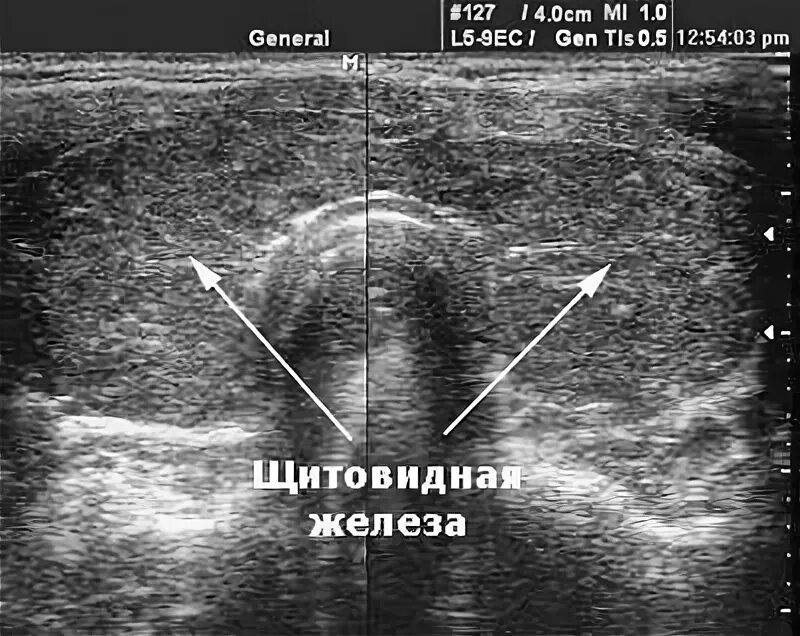

Выраженные диффузные изменения щитовидной железы